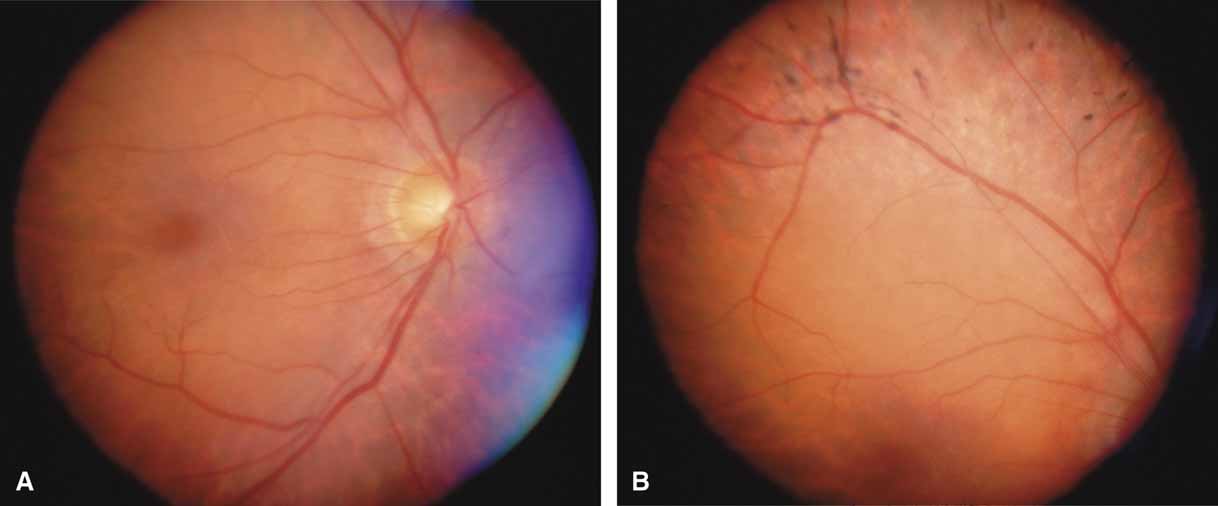

The possible association between retinitis pigmentosa and glaucoma dates back to 1862.11 Over the past century the reported glaucoma incidence has varied between 2.98% to 10% of all cases of retinitis pigmentosa.12,13 Of concern in all previous reports is the accuracy of the diagnosis of retinitis pigmentosa itself, a hereditary disease with diverse manifestations. Retinitis pigmentosa-like syndromes may mimic glaucomatous field loss, and the pattern of advancement of visual field loss in true retinitis pigmentosa may parallel that of typical open-angle glaucoma. Patients with undiagnosed retinitis pigmentosa may have subtle fundus findings, especially those with the sine pigmento form (Fig. 1). A clue to diagnosis is the disproportionate peripheral field loss in comparison to the degree of optic nerve cupping and rim pallor. Patients with atypical field loss and minimal optic nerve cupping should have an electroretinogram to exclude unsuspected retinitis pigmentosa.